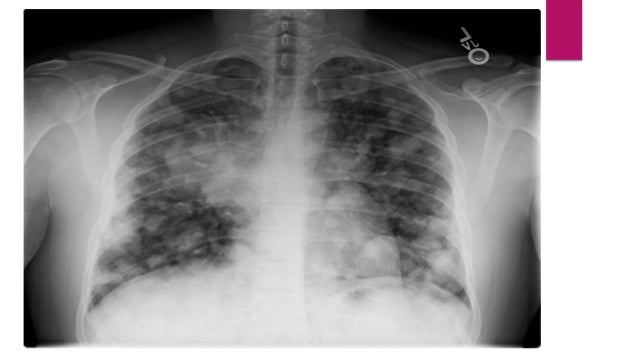

It is seen in cystic bronchiectasis here in this xaray there are nodular shadows bilateral more in lwr zns slightly more on rt side dd macro milliary lymphangitis carcinomatosis ild multiple bilateral secondaries.

Snowstorm sign on breast ultrasound imaging represents the presence of free silicone droplets mixed with breast tissue giving a characteristic heterogeneous echogenic appearance with dispersion of the ultrasound beam. It is seen in cystic bronchiectasis here in this xaray there are nodular shadows bilateral more in lwr zns slightly more on rt side dd macro milliary lymphangitis carcinomatosis ild multiple bilateral secondaries. Can be seen in tb,mets,sarcoidosis,pap,fungal infections,cwp. Snowstorm sign on breast ultrasound imaging represents the presence of free silicone droplets mixed with breast tissue giving a characteristic heterogeneous echogenic appearance with dispersion of the ultrasound beam. It is considered the most reliable sign of extracapsular breast implant rupture 1.a similar appearance may be seen in axillary nodes in.